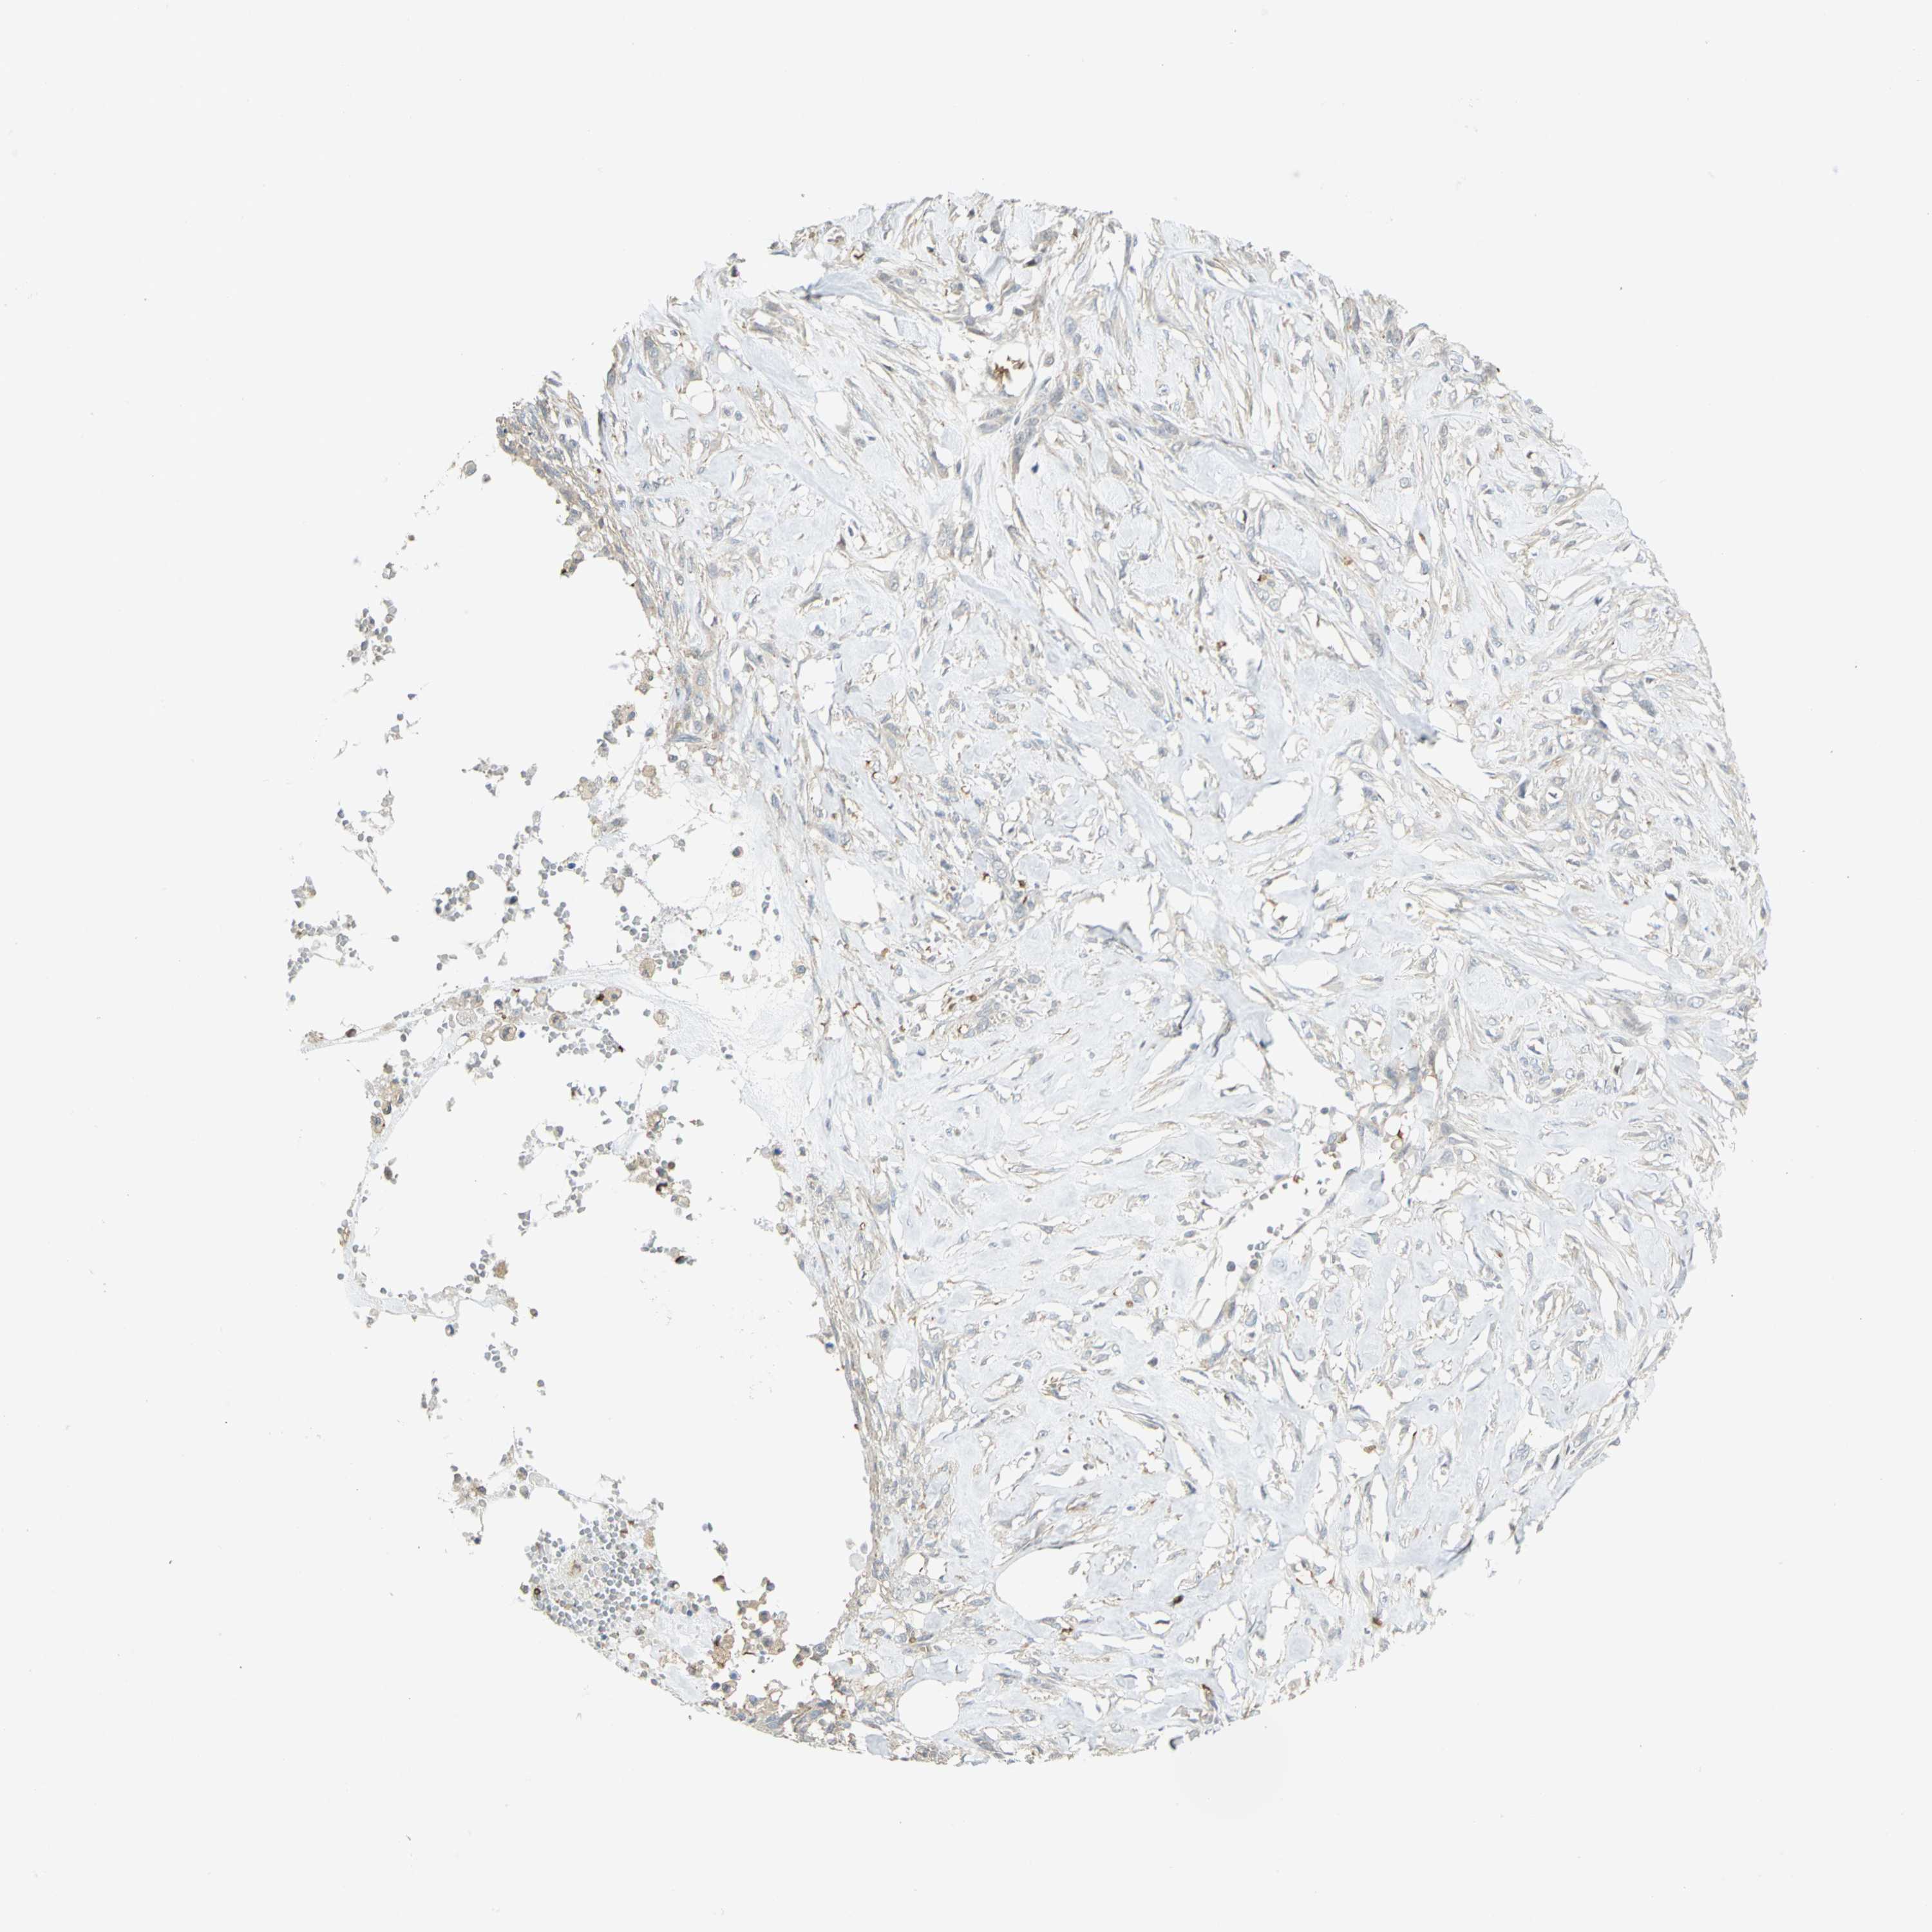

SKIN CANCER - Protein expressioni

A mouse-over function shows sample information and annotation data. Click on an image to view it in a full screen mode. Samples can be filtered based on level of antibody staining by selecting one or several of the following categories: high, medium, low and not detected. The assay and annotation is described here.

Antibody stainingi

Antibody staining in the annotated cell types in the current human tissue is reported as not detected, low, medium, or high, based on conventional immunohistochemistry profiling in selected tissues. This score is based on the combination of the staining intensity and fraction of stained cells.

Each image is clickable and will lead to virtual microscopy that enables deeper exploration of all samples and also displays staining intensity scores, fraction scores and subcellular localization as well as patient and tissue information for each sample.

Antibody HPA004842

Antibody HPA056953

Staining

High

Medium

Low

Not detected

Intensity

Strong

Moderate

Weak

Negative

Quantity

>75%

75%-25%

<25%

None

Location

Nuclear

Cytoplasmic/membranous

Cytoplasmic/membranous,nuclear

Squamous cell carcinoma, NOS

Basal cell carcinoma